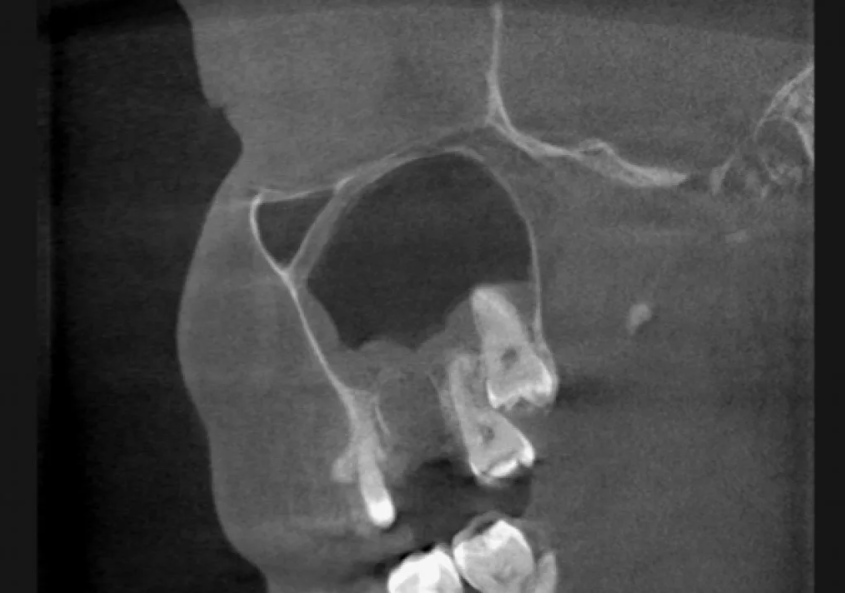

Сегодня мы с вами разберем сложную и крайне важную тему в челюстно-лицевой хирургии – пластику альвеолярного отростка верхней челюсти при наличии ороантрального сообщения (ОАС) с применением современных остеопластических материалов. Суть проблемы ороантрального сообщения Ороантральное сообщение – это патологическое соустье (отверстие) между полостью рта (перед этим) и верхнечелюстной пазухой (синусом). Наиболее частая причина его возникновения – ятрогенное осложнение после удаления моляров и премоляров на верхней челюсти, корни которых анатомически тесно связаны с дном гайморовой пазухи. Небольшое перфоративное отверстие, диагностированное и ушитое сразу, чаще всего не имеет последствий. Однако недиагностированное, неушитое или инфицированное сообщение приводит к хроническому синуситу и формированию стойкого свищевого хода, эпителизированного по краям, который самостоятельно уже не закроется. Именно в такой ситуации требуется комплексное хирургическое вмешательство – пластика альвеоля

Ороантральное сообщение – это патологическое соустье (отверстие) между полостью рта (перед этим) и верхнечелюстной пазухой (синусом). Наиболее частая причина его возникновения – ятрогенное осложнение после удаления моляров и премоляров на верхней челюсти, корни которых анатомически тесно связаны с дном гайморовой пазухи.

Небольшое перфоративное отверстие, диагностированное и ушитое сразу, чаще всего не имеет последствий. Однако недиагностированное, неушитое или инфицированное сообщение приводит к хроническому синуситу и формированию стойкого свищевого хода, эпителизированного по краям, который самостоятельно уже не закроется. Именно в такой ситуации требуется комплексное хирургическое вмешательство – пластика альвеолярного отростка с устранением дефекта.